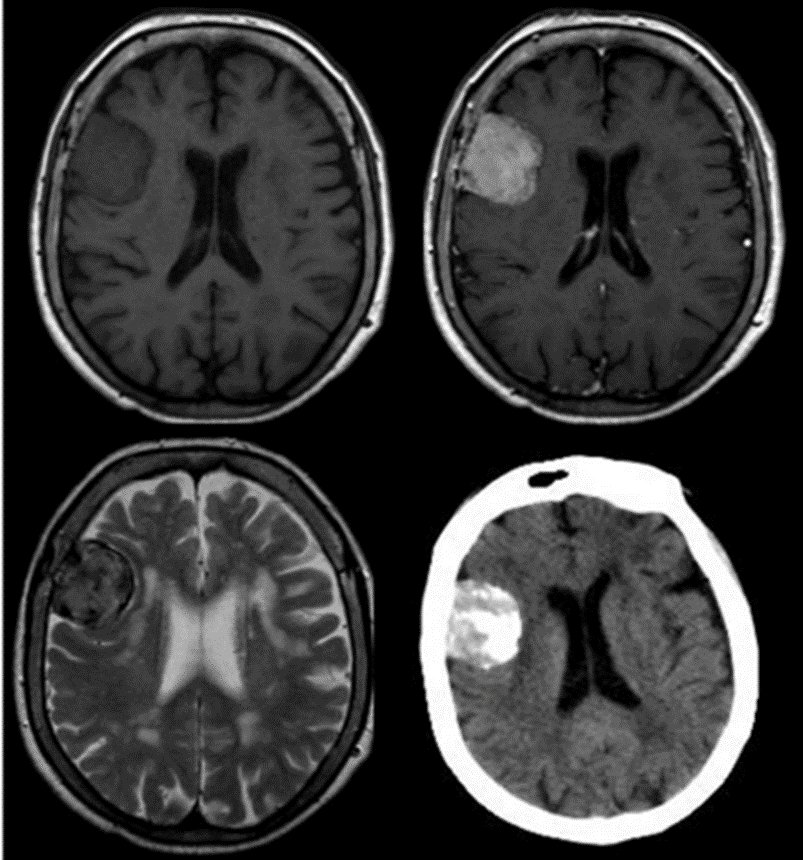

En cuanto a las características de estos tumores en RMI es ampliamente aceptado que las calcificaciones y un comportamiento iso-hipointenso en secuencia T2 está asociado a nulo o muy lento crecimiento (fig 1). El edema peritumoral ponderado en secuencia T2 es un factor para indicación quirúrgica de inicio o un seguimiento estrecho ya que implica mayor tasa de crecimiento 2,3. Para el seguimiento por imágenes es importante un protocolo de control basado en volumetría tumoral y un registro de las curvas de crecimiento. Las medidas lineales, sobre todo en fosa posterior, y la apreciación subjetiva del especialista en diagnóstico por imágenes puede llevar a confusión 4,5,9.

Figura 1: RMN y TAC de paciente de 82 años con imágenes compatible con MI, Isointenso en T1 y realce con gadolinio e Hipointenso en T2, tumor calcificado confirmado por la TAC. La paciente fue seguida durante 8 años sin cambios clínicos ni imagenológicos.